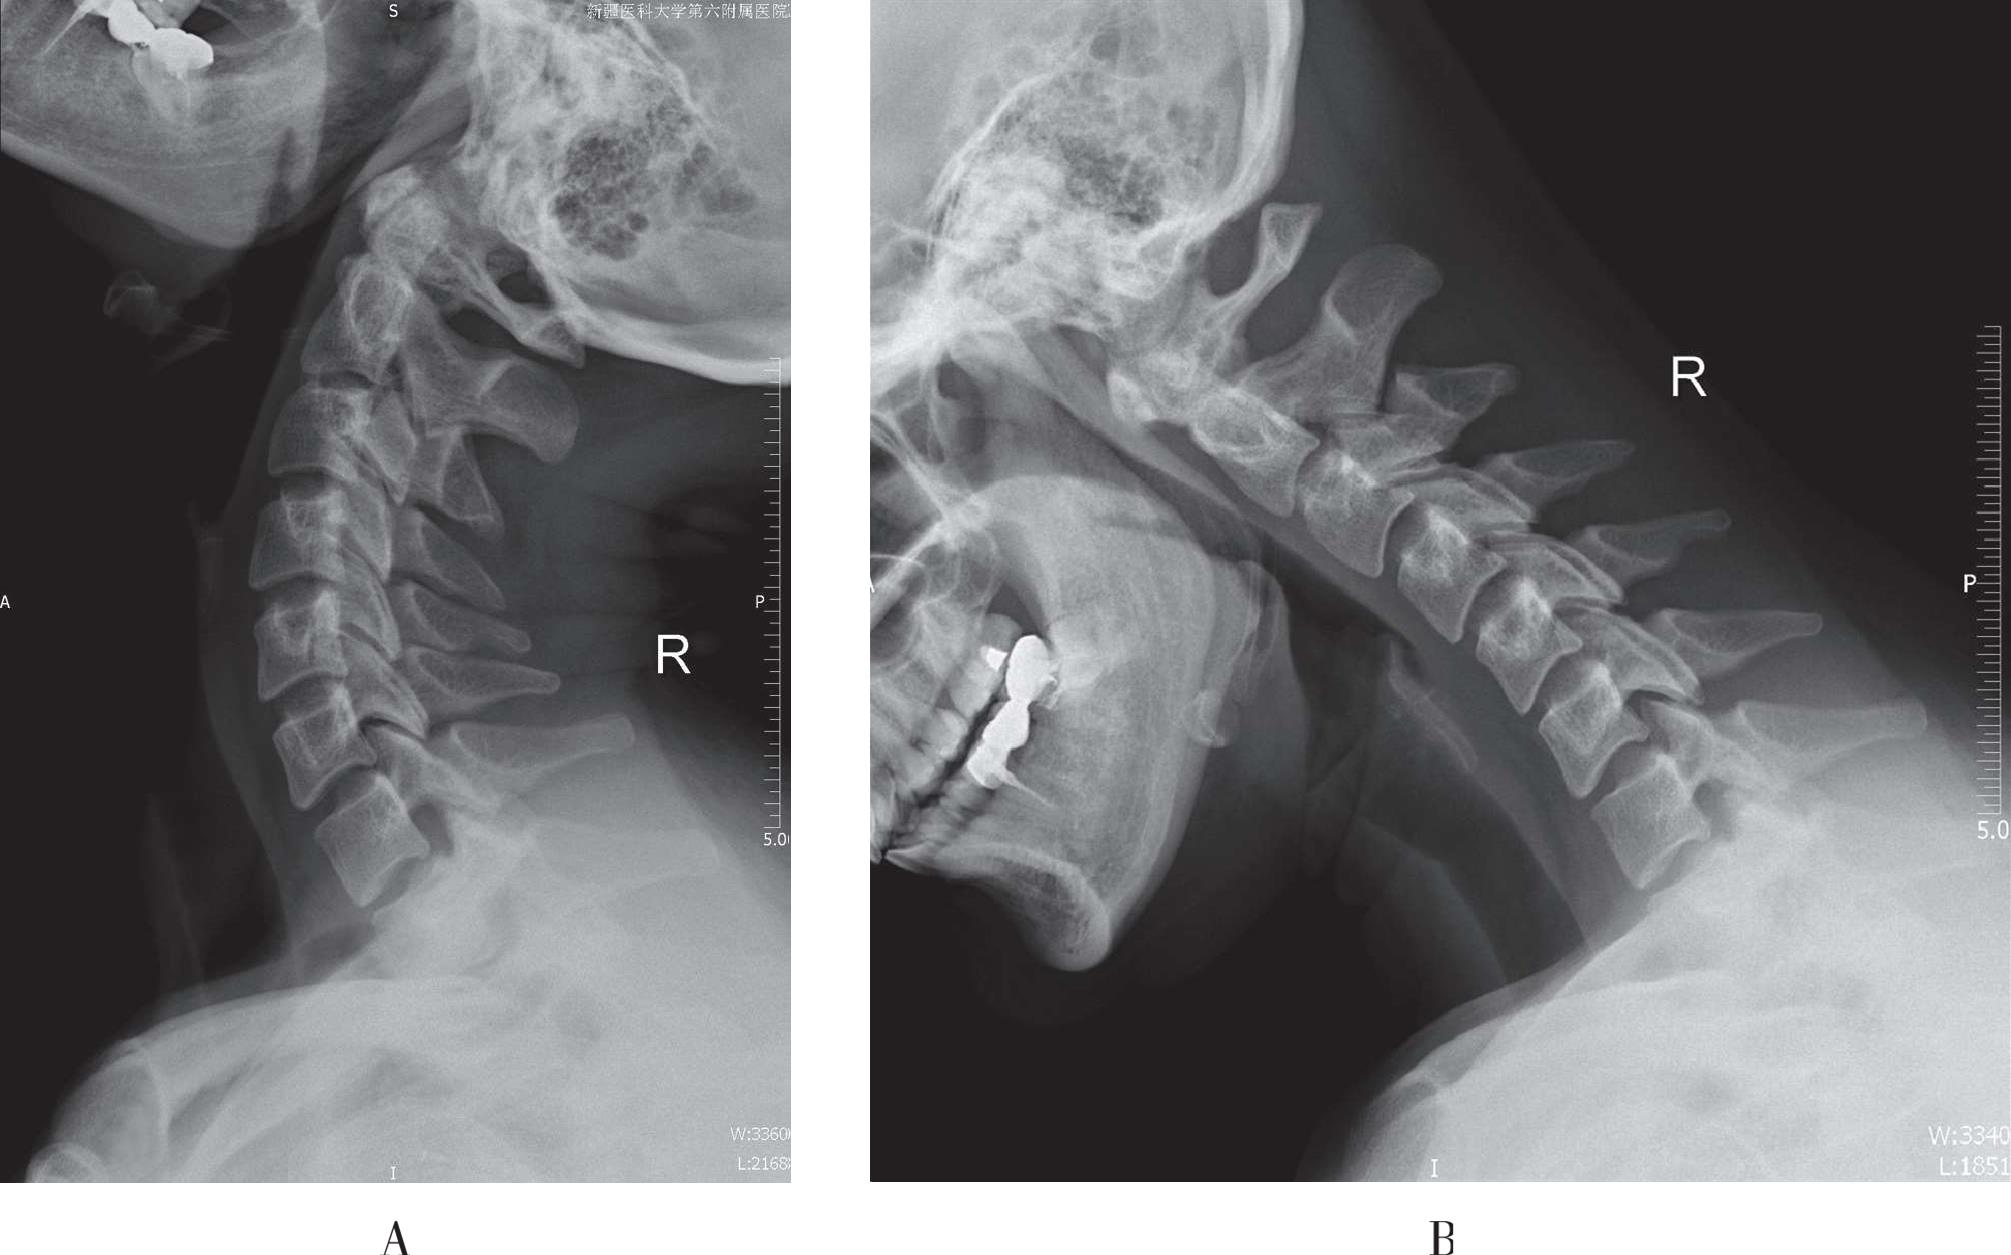

过度伸展或屈曲后摄标准侧位X线片,观察颈椎的生理曲度、运动幅度和椎间隙(图3-9、3-10)。颈椎急性损伤不宜采用此方法。

A. 颈椎后屈位X线片;B. 颈椎前屈位X线片

图3-10 颈椎运动位X线片